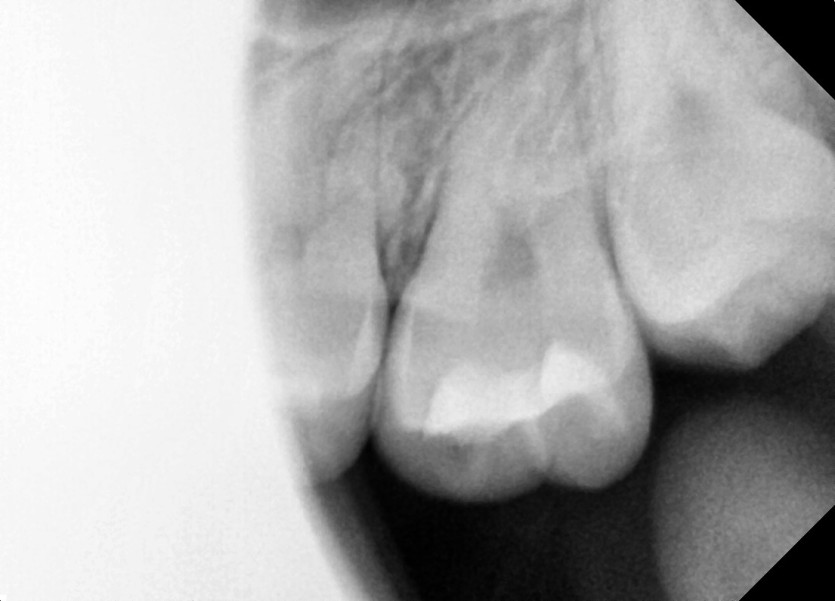

#28,38 사랑니 발치

구강 외과 전문의가 당일 발치했습니다.